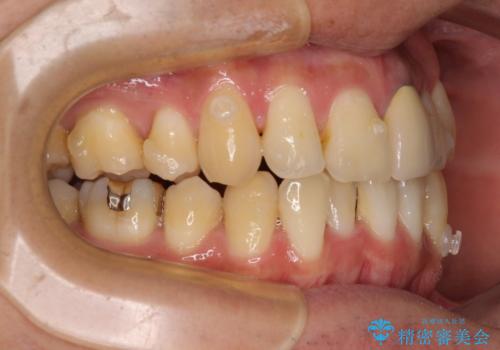

- 下顎の八重歯を気にして来院された患者様です。

左下以外、3本の第一小臼歯が既に抜去されており、左下は八重歯になっている状態でした。

左下の八重歯は手前に傾斜していたため、インビザラインによる抜歯矯正が可能と判断し、後方にある第一小臼歯を抜歯してインビザラインにて矯正治療を行うこととしました。

ワイヤー矯正と比較すると、八重歯が後方に傾斜した仕上がりとなりましたが、患者様ご希望のインビザラインにて十分な歯列を達成することができました。